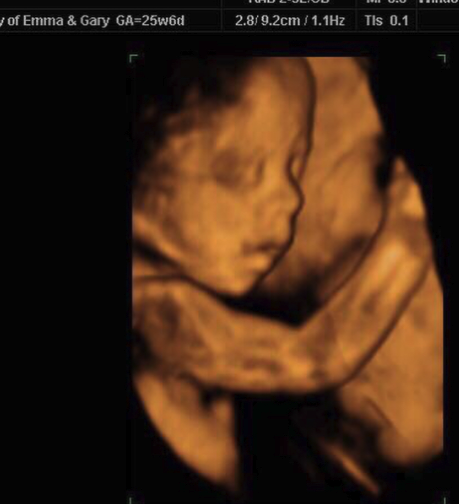

They arrived Thursday evening and we got straight to it, checking well-being and measurements. Their 2D images were fab, with a wonderful side profile. Baby had a good strong heartbeat and was a perfect and healthy size. We then moved on to 4D…and all we can say is that during the scan, baby was not shy. Taking after Mummy and Daddy, baby was pouting, showing off his biceps all combined with an adorable button nose. Baby was very content during the scan, even cracking the odd smile.

“Little Poser”– Gary and Emma were delighted with their images